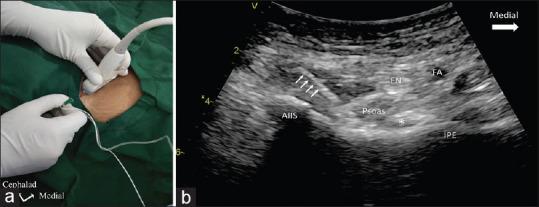

Peri-capsular nerve group block provides excellent analgesia in hip fractures and positioning for spinal anaesthesia: A prospective cohort study.

Indian J Anaesth. 2020 Oct;64(10):898-900. doi: 10.4103/ija.IJA_450_20. Epub 2020 Oct 1.

Pericapsular Nerve Group (PENG) Block for Hip Fracture.髋关节骨折的囊周神经群(PENG)阻滞。

Reg Anesth Pain Med. 2018 Nov;43(8):859-863. doi: 10.1097/AAP.0000000000000847.